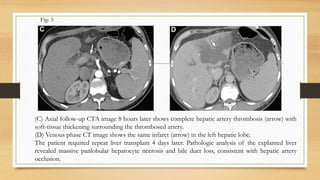

(C) Axial follow-up CTA image 8 hours later shows complete hepatic artery thrombosis (arrow) with

soft-tissue thickening surrounding the thrombosed artery.

(D) Venous phase CT image shows the same infarct (arrow) in the left hepatic lobe.

The patient required repeat liver transplant 4 days later. Pathologic analysis of the explanted liver

revealed massive panlobular hepatocyte necrosis and bile duct loss, consistent with hepatic artery

occlusion.